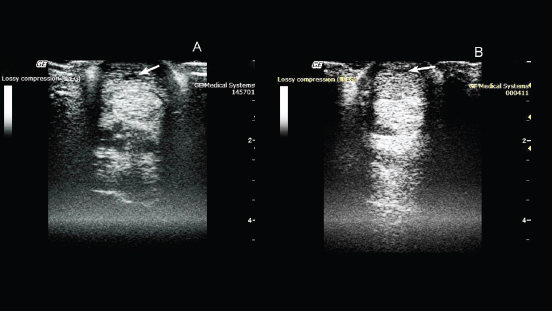

Fig. 1. Ultrasonography of the superficial digital flexor. (A): Before the introduction of plasmid DNA. (B): 20th day after the introduction of plasmid DNA.

Therapeutic efficacy and the regenerative effect of the drug (pDNA) on connective tissues were studied in a 2-year-old pure-bred Arabian stallion with damage to the superficial extensor. During clinical examination, it was observed that the horse was limping on the left forelimb. The degree of lameness was rated 2 out of 5 (according to the 5-point lameness scale (2) AAEP). The pronounced anechoic and hypoechoic zones at the back of the limb was visualized using ultrasound examination of the damaged leg (Fig. 1). A diagnosis of tendonitis of the superficial digital flexor was made.

On the 20th day after drug administration, the absence of lameness and lack of swelling at the site of damage were observed. An ultrasound scan showed an increase in the degree of echogenicity and a decrease in the hypoechoic region of the damaged area (Fig. 1).